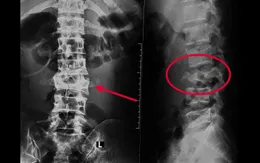

Cần Thơ: Cứu bệnh nhân leo dừa té gãy xương cột sống

VTV.vn - Các bác sĩ Khoa Ngoại Thần kinh, Bệnh viện Đa khoa Trung ương Cần Thơ vừa phẫu thuật thành công, cứu sống bệnh nhân bị gãy cột sống, nguy cơ tử vong cao.